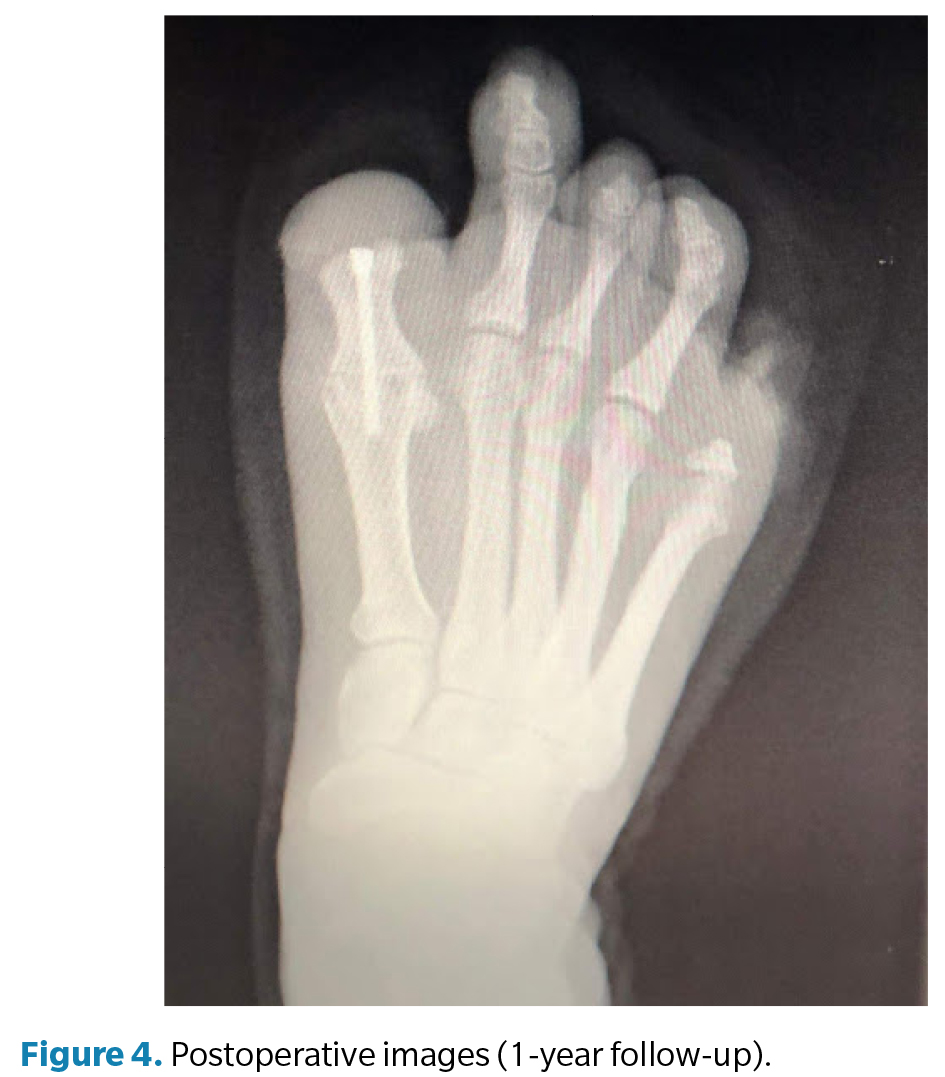

La cirugía (Figura 3) se realizó en marzo de 2022 bajo anestesia regional mediante bloqueo poplíteo posterior con sedación consciente supervisada por anestesiólogo. Se administró profilaxis antibiótica con cefazolina 2 g por vía intravenosa 30 min antes de la incisión y se utilizó torniquete neumático a nivel del tobillo, con presión controlada (a 250 mm Hg) y tiempo de isquemia limitado a 45 min. Se efectuó un abordaje dorsal longitudinal sobre la primera articulación metatarsofalángica, respetando las estructuras neurovasculares. Se identificaron los restos óseos irregulares de la falange proximal y se realizó su resección completa, seguida de remodelado de los márgenes óseos hasta obtener superficies regulares y viables. Posteriormente, se prepararon las superficies articulares de la primera metatarsofalángica mediante fresado y curetaje hasta lograr una base sangrante adecuada para la artrodesis. La posición de fusión se determinó intraoperatoriamente mediante pruebas de carga, fijando el hallux en aproximadamente 10° de dorsiflexión respecto al plano del suelo, con el fin de optimizar la propulsión y evitar la sobrecarga plantar en el muñón residual. La fijación definitiva se realizó con 1 tornillo canulado tipo Herbert, verificándose estabilidad intraoperatoria y correcta alineación mediante fluoroscopia (Figura 4). El procedimiento concluyó sin incidencias, con hemostasia cuidadosa y cierre por planos.

El postoperatorio incluyó curas secas periódicas y seguimiento funcional progresivo. A los 3 meses de la intervención se constató resolución completa del dolor y mejoría significativa en la calidad de la marcha. A los 6 meses la paciente presentó recupe­ración funcional satisfactoria, por lo que se procedió al alta médica temporal. Posteriormente se confeccionaron prótesis digitales de silicona personalizadas para ambos pies, destinadas a mejorar la simetría podológica, la distribución de cargas y la aceptación psicosocial. En el seguimiento a los 12 meses, la paciente se mantenía asintomática, con consolidación radiográfica completa de la artrodesis, alineación correcta del primer radio y marcha estable sin limitaciones, confirmando el éxito funcional del procedimiento.